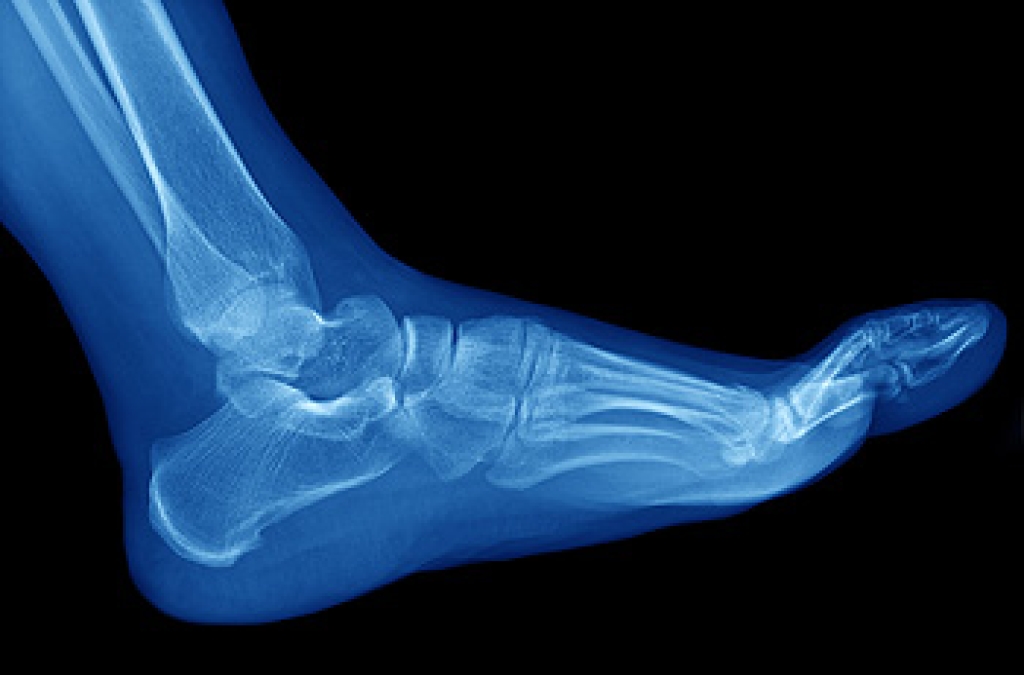

Stress fractures develop when a bone that’s constantly under stress eventually weakens. It typically occurs on the outside of the bone and happens due to repetitive motion. Many professional athletes and runners develop this condition, as overuse of the bones in the foot is common. The way the foot is structured may be another cause, as having flat feet or higher arches may be a contributing factor in developing stress fractures. When overdoing a specific activity, the risk is high for developing these fractures. There may not be physical signs and symptoms from the fracture, but when the activity resumes, pain is often felt. An x-ray is used to determine exactly where the fracture is. Recovery comes from resting the foot and being careful not to put stress on the bones. Occasionally a medical boot is worn to keep the fracture from worsening, in addition to engaging in physical therapy. Please seek the advice of a podiatrist if you feel you have a stress fracture in the foot or ankle.

Stress fractures occur in the foot and ankle when muscles in these areas weaken from too much or too little use. The feet and ankles then lose support when walking or running from the impact of the ground. Since there is no protection, the bones receive the full impact of each step. Stress on the feet can cause cracks to form in the bones, thus creating stress fractures.